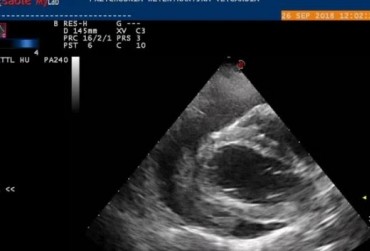

Metody małoinwazyjne w kardiologii weterynaryjnej. Czy chirurg jest jeszcze potrzebny? Opis przypadku

Artykuł przedstawia różne metody usunięcia worka osierdziowego. Prezentuje zarówno metody klasyczne, jak i małoinwazyjne, pokazując zalety i wady każdej z nich. Dzięki przedstawionemu opisowi przypadku pozwala zrozumieć, czym należy się kierować przy wyborze odpowiedniej metody operacji.